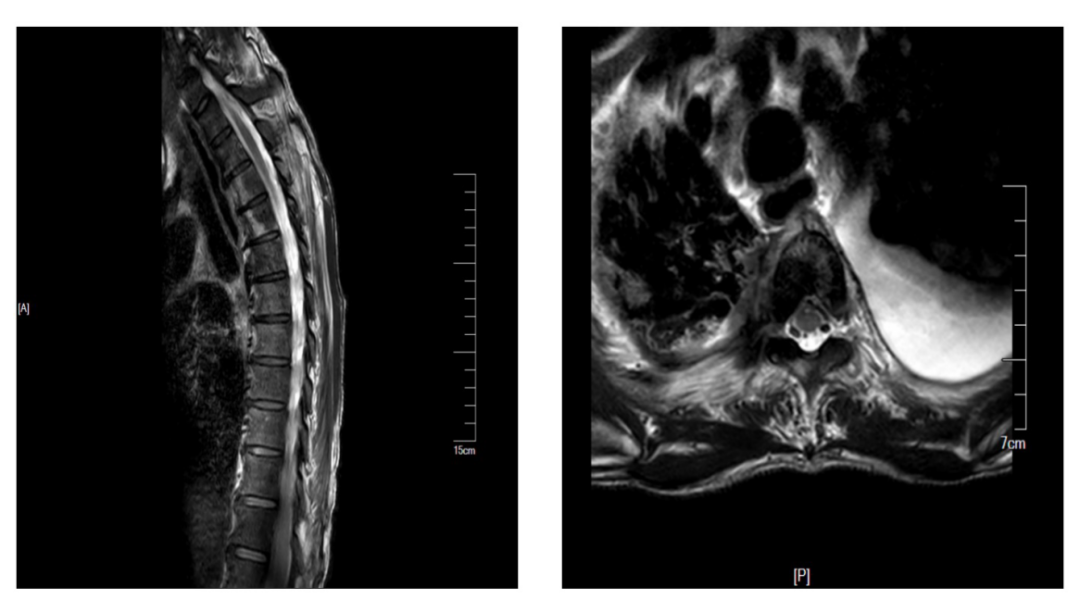

影像检查:胸椎MRI提示T3-T6椎体及附件可见低信号影,压脂序列信号增高,T4、5椎体为著,临近软组织T2W1信号稍高(图1)。

图1胸椎MRI平扫